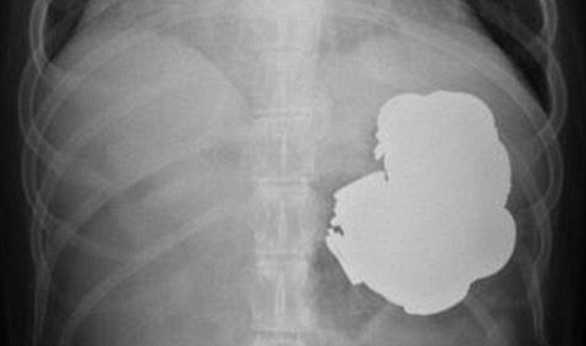

ذكرت صحيفة ديلى ميل البريطانية، أن الأطباء عثروا في معدة فلاح هندي يدعى راجبال سينغ 34 عاما، على مئات من العملات والمسامير بعد أن ابتلعهم لأنه كان "مكتئبا".

وأضافت أن الفلاح الهندى ظل يأكل أجسام معدنية 3 سنوات، ليصبح عدد ما ابتلعه حوالي 140 قطعة نقدية، و150 مسمار، ونقلت الصحيفة عن "سينغ" قوله: "إنه خضع لـ240 عملية جراحية لإزالة الأجسام المعدنية".